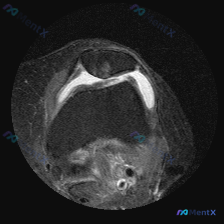

看到一份膝关节轴位MRI的读片资料,软骨异常是核心发现,整理了影像特征和完整分析思路,和大家分享讨论。 一、影像基本信息 这是膝关节髌股关节层面的脂肪抑制序列MRI(PD-FS或T2-FS),图像特征: 1. 髌骨、股骨皮质低信号,骨髓脂肪信号正常 2. 核心异常:髌骨后方关节软骨信号不均匀,局部高...

刚看到这份膝关节轴位MRI的分析资料,整理一下思路,这个病例其实挺容易踩坑的,分享给大家一起讨论。 病例影像核心信息 本次提供的是膝关节轴位MRI(T2WI/质子密度脂肪抑制序列),核心发现如下: 1. 髌股关节:髌骨软骨面全层高信号改变,股骨滑车中央及内侧软骨也可见广泛高信号;髌股关节间隙可见明显...

刚看到一例膝关节MRI读片的病例,整理了完整的影像发现和分析思路分享给大家,这个病例其实挺容易踩坑的。 病例影像资料 这是膝关节MRI T2序列轴位图像,读片结果整理如下: 1. 髌股关节: 髌骨后方关节软骨不连续,信号增高、形态毛糙,可见片状高信号,提示软骨损伤磨损;股骨滑车关节面软骨同样信号增高...